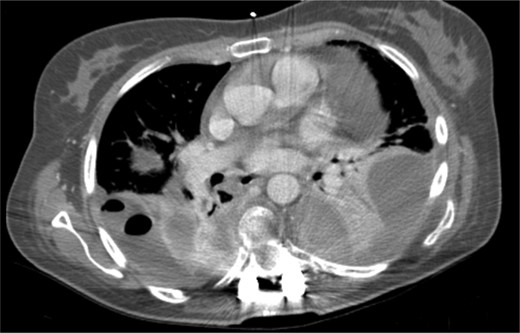

It was only by the 19th postoperative day, which the patient showed worsening of her general status with fever, dyspnea, decreased gas exchange and an increase in inflammatory markers. A new CT scan was performed, revealing a moderate fluid collection in both lungs, compatible with empyema (Fig. 5). The patient evolved to a septic state, which required her to be transferred to the intensive care unit.

Postoperative thoracic CT scan; large septated empyema, extending from the surgical site to both pleural cavities, was found to be the cause of deterioration of the patient's general condition.